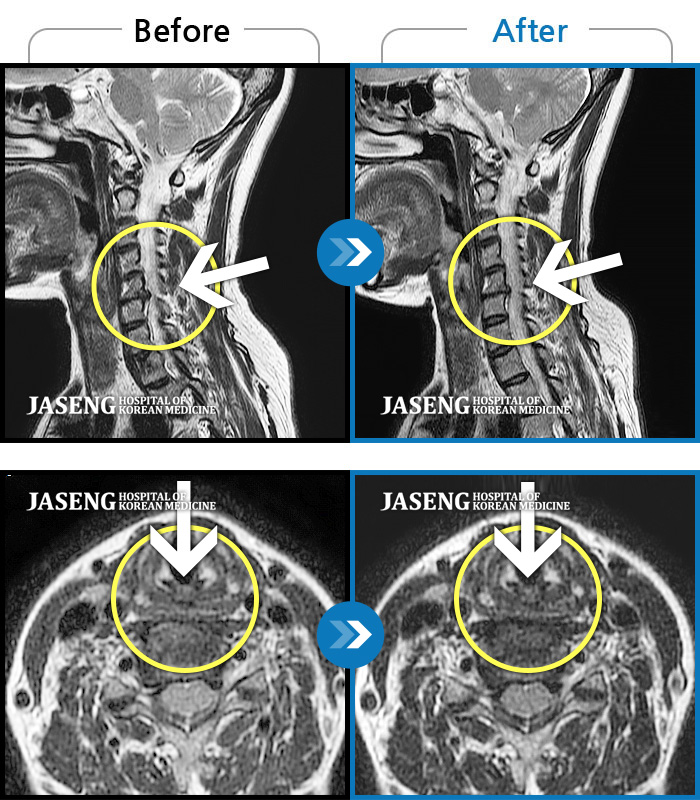

목디스크

도움받은 사례

인천 · 강아현 원장

좌측 목 통증 및 견갑내연 통증, 팔 전체 통증으로 일상생활에 어려움을 겪는 상태로 내원하셨습니다.

촬영시기

2023.11.27 ~ 2024.05.27

2024.06.03

조회수 481